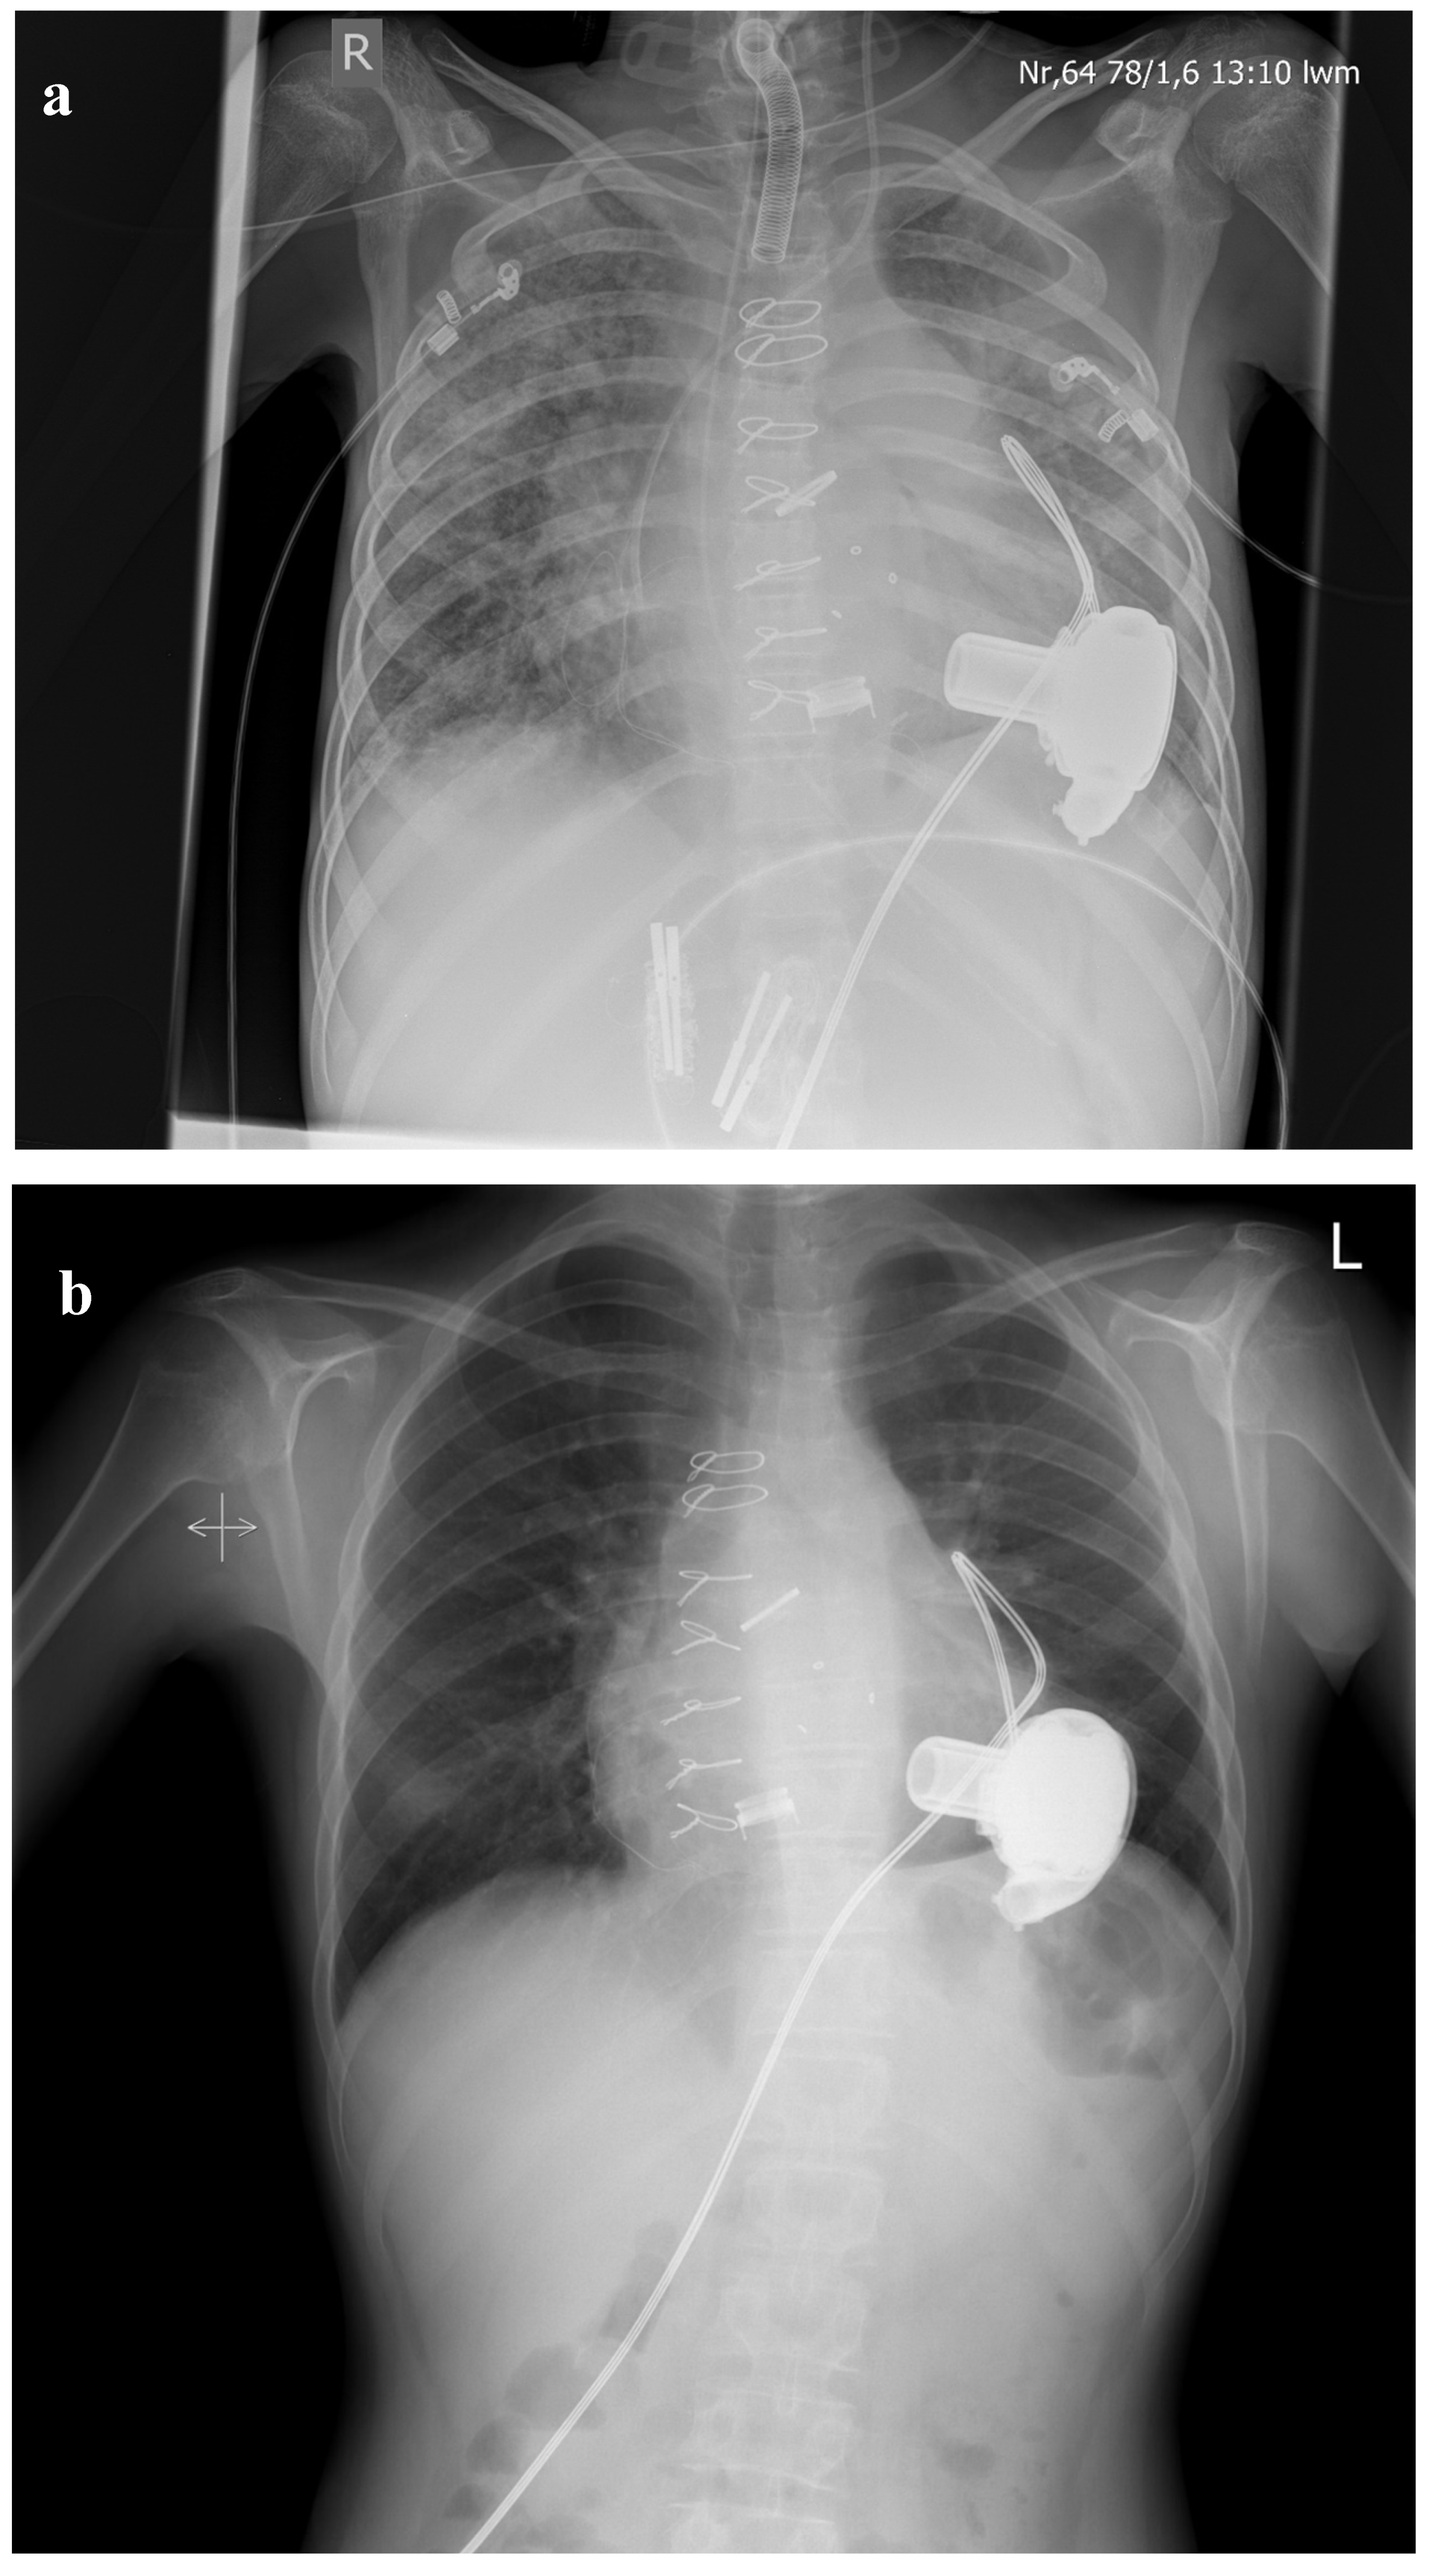

End-Stage/Bridging Treatment Strategies

- Bauer, A.; Khalil, M.; Schmidt, D.; Bauer, J.; Esmaeili, A.; Apitz, C.; Voelkel, N.F.; Schranz, D. Creation of a restrictive atrial communication in pulmonary arterial hypertension (PAH): Effective palliation of syncope and end-stage heart failure. Pulm. Circ. 2018, 8. [Google Scholar] [CrossRef] [PubMed] [Green Version]

- Akintürk, H.; Sen-Hild, B.; Yörüker, U.; Müller, M.; Thul, J.; Jux, C.; Schranz, D. Reverse Potts-Shunt for Bridging to Transplant, Recovery or Long-term Palliation. Thorac. Cardiovasc. Surg. 2018, 66, 71. [Google Scholar] [CrossRef]

- Schranz, D.; Akintuerk, H.; Voelkel, N.F. ‘End-stage’ heart failure therapy: Potential lessons from congenital heart disease: From pulmonary artery banding and interatrial communication to parallel circulation. Heart 2016, 103, 262–267. [Google Scholar] [CrossRef] [PubMed] [Green Version]